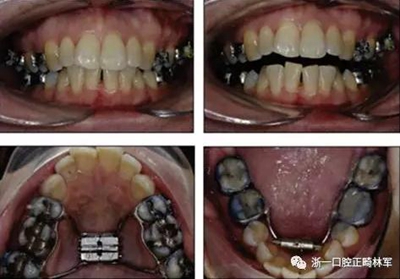

術后第9天開始旋轉擴弓器,每天轉2次,每次轉90度,即擴開0.5mm。每隔1周進行檢查,目標上頜擴開9mm,下頜擴開6mm。18天后,上頜中切牙間出現8mm間隙。下頜出現6mm間隙,(于13天出現后,停止旋轉擴弓器)。在擴弓器旋轉3天后,拍片發(fā)現左下頜中切牙遠中牙根中段有一條低密度陰影,臨床冷熱診反應遲鈍,可能為術中損傷所致。牙體牙髓科會診,建議行根管治療,故行根管治療。

擴弓保持8周后,除擴弓器影響牙外粘接托槽,使用0.014鎳鈦絲進行排齊、整平。旋轉停止后3個月拆除擴弓器,全口粘接托槽,使用0.016niti繼續(xù)排齊整平。佩戴可摘保持器,保持上頜寬度。在使用至0.018x0.018niti7周,徹底排齊整平后,使用大弓型的0.016x0.022不銹鋼絲,繼續(xù)維持原有寬度,同時停止使用可摘保持器。掛II類牽,糾正磨牙關系,使用鏈圈關閉散在間隙,少量使用IPR去除局部前牙的黑三角。術后9個月拍全景示,牙根平行度可,再無其他牙根出現問題。1年7個月后治療結束。上下頜3-3舌側保持器+哈雷氏保持器進行保持。

患者側貌改善,下唇唇肌緊張消失,上下唇可自然閉合。磨牙及尖牙關系糾正至I類,覆合覆蓋正常。上下頜弓型糾正至卵圓形,牙弓寬度增加。頭影測量分析示SNA角81.8°,ANB角3°。頭影測量重疊圖示下頜骨向后旋轉,垂直面高度略有增加。

19個月后復查,情況穩(wěn)定,牙弓寬度穩(wěn)定。